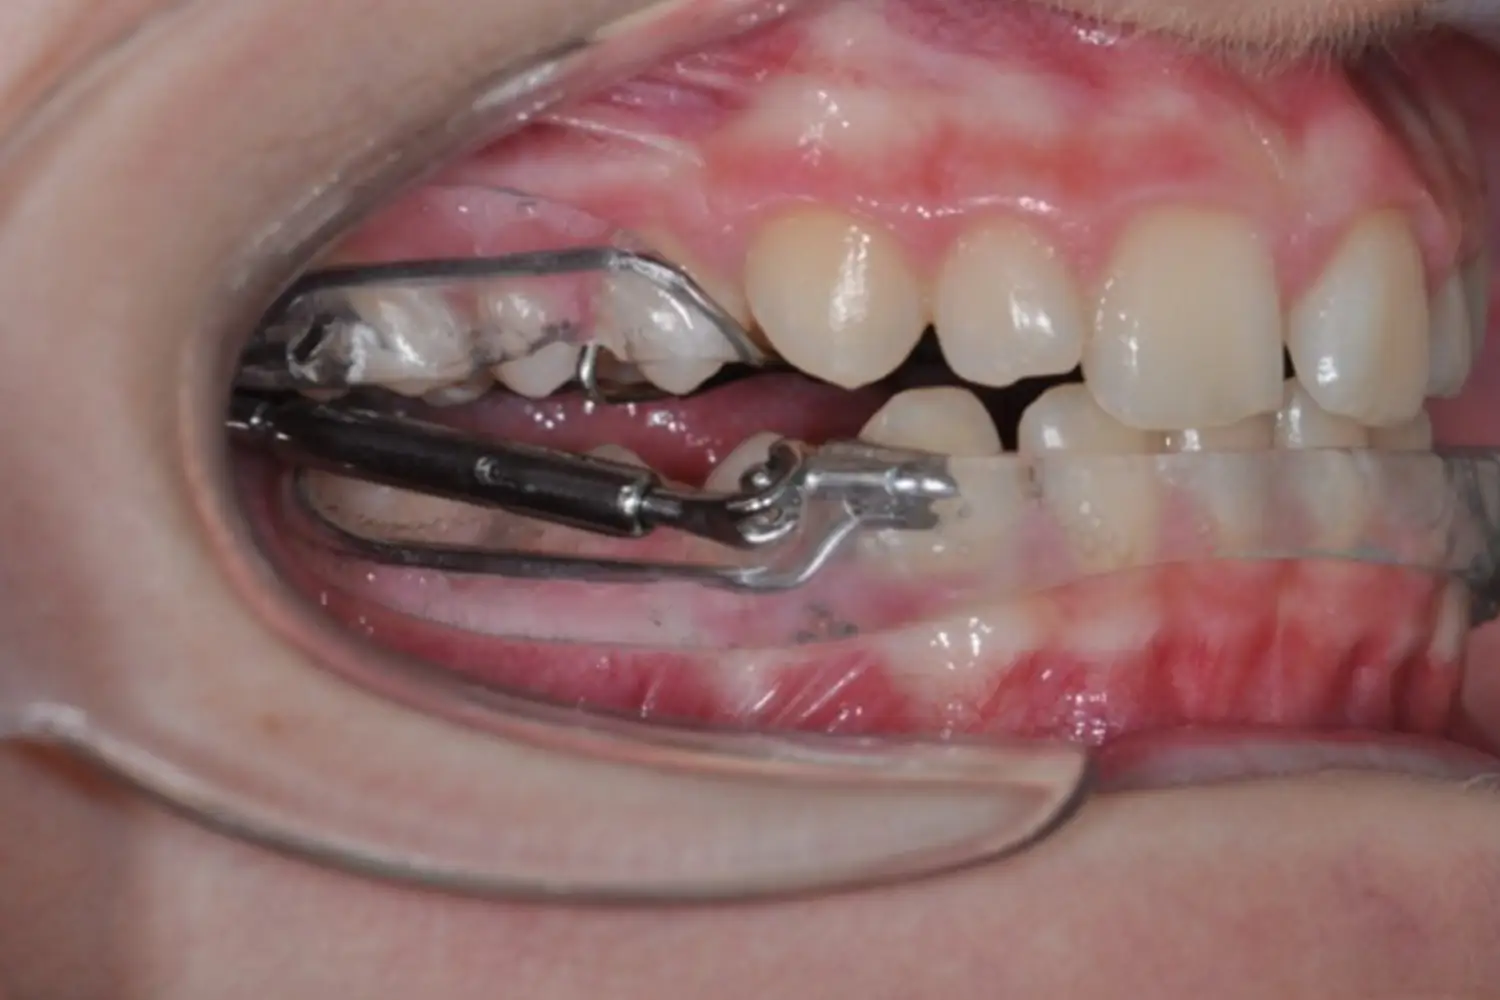

Les Traitements d'Interception

Les traitements d’interception sont des traitements de l’enfant jeune, lorsqu’il lui reste encore des dents de lait. C’est pourquoi nous vous recommandons de consulter dès que votre enfant a 7 ou 8 ans.

En effet, même si le patient n’a pas encore toutes ses dents définitives, il est parfois important de le soigner tôt dans sa croissance, notamment pour corriger les problèmes de décalage entre les mâchoires, ou lorsqu’il n’y a pas assez de place dans sa bouche pour que toutes ses dents définitives puissent pousser.

Ces traitements sont courts, avec des appareils simples, et une fois le problème de manque de place ou de décalage des mâchoires corrigé, nous surveillons la croissance et l’éruption des dents de votre enfant, pour qu’elles se fassent dans les meilleures conditions.